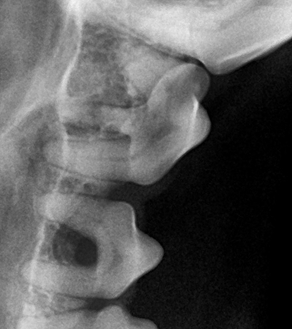

치주염은 진행 정도에 따라 1~4기로 분류되며, 기수에 따라 관리 방법과 치료 방향이 달라집니다.

| 1기 (경도) | 잇몸 가장자리에 염증 발생 | 입 냄새 시작, 이빨 누르면 잇몸 붉어짐 |

| 2기 (중등도) | 염증이 치아 주변까지 확산 | 냄새 심해짐, 딱딱한 사료 꺼림 |

| 3기 (중증) | 치아 지지 조직 파괴 시작 | 이빨 흔들림, 침 흘림 |

| 4기 (중증 이상) | 치아 탈락, 고름, 턱뼈 침범 가능성 | 심한 통증, 입 주변 부음, 만성 염증 |